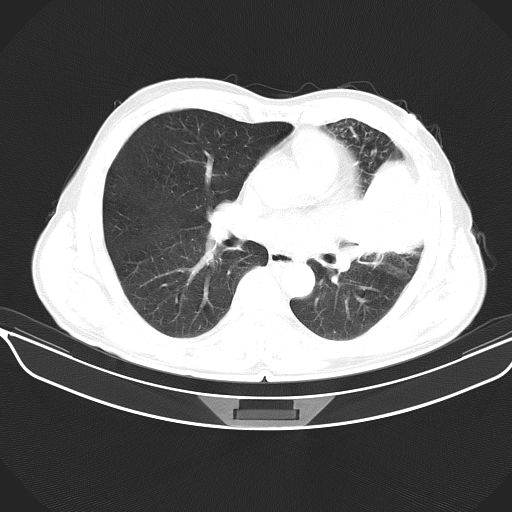

以下是引用心路寻觅在2010-3-1 10:23:00的发言:[br]1、考虑左肺上叶周围型肺癌[br]2、右上肺陈旧性病灶。[br][br][本贴已被 心路寻觅 于 2010-3-1 10:40:18 修改过]

以下是引用shuiyuan在2010-3-1 10:45:00的发言:[br]考虑左肺上叶中心型肺癌伴阻塞型炎症,邻近胸膜受侵。